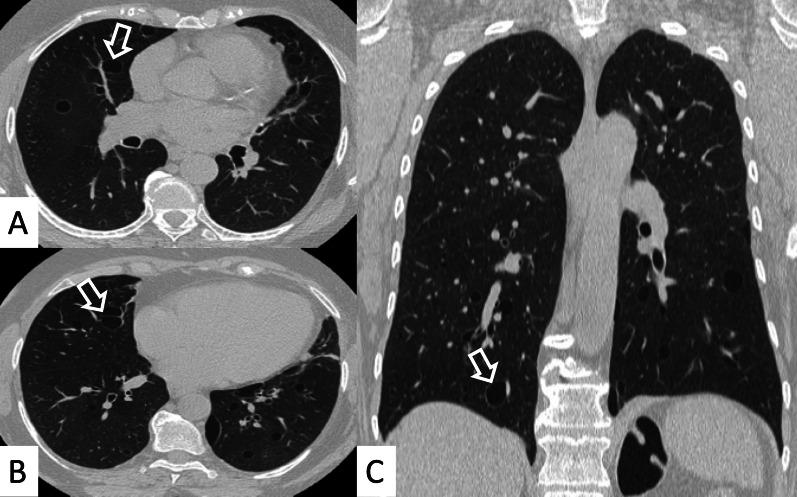

Connective tissue diseases (CTDs) include a spectrum of disorders that affect the connective tissue of the human body; they include autoimmune disorders characterized by immune-mediated chronic inflammation and the development of fibrosis. Lung involvement can be misdiagnosed, since pulmonary alterations preceded osteo-articular manifestations only in 20% of cases and they have no clear clinical findings in the early phases. All pulmonary structures may be interested: pulmonary interstitium, airways, pleura and respiratory muscles. Among these autoimmune disorders, rheumatoid arthritis (RA) is characterized by usual interstitial pneumonia (UIP), pulmonary nodules and airway disease with air-trapping, whereas non-specific interstitial pneumonia (NSIP), pulmonary hypertension and esophageal dilatation are frequently revealed in systemic sclerosis (SSc). NSIP and organizing pneumonia (OP) may be found in patients having polymyositis (PM) and dermatomyositis (DM); in some cases, perilobular consolidations and reverse halo-sign areas may be observed. Systemic lupus erythematosus (SLE) is characterized by serositis, acute lupus pneumonitis and alveolar hemorrhage. In the Sjögren syndrome (SS), the most frequent pattern encountered on HRCT images is represented by NSIP; UIP and lymphocytic interstitial pneumonia (LIP) are reported with a lower frequency. Finally, fibrotic NSIP may be the interstitial disease observed in patients having mixed connective tissue diseases (MCTD). This pictorial review therefore aims to provide clinical features and imaging findings associated with autoimmune CTDs, in order to help radiologists, pneumologists and rheumatologists in their diagnoses and management.

结缔组织病(CTDs)包括一系列影响人体结缔组织的疾病;它们包括以免疫介导的慢性炎症和纤维化发展为特征的自身免疫性疾病。肺部受累可能会被误诊,因为肺部改变仅在20%的病例中先于骨关节炎表现出现,且在早期阶段没有明确的临床发现。所有肺部结构都可能受累:肺间质、气道、胸膜和呼吸肌。在这些自身免疫性疾病中,类风湿关节炎(RA)的特征是普通型间质性肺炎(UIP)、肺结节和伴有空气潴留的气道疾病,而系统性硬化症(SSc)常表现为非特异性间质性肺炎(NSIP)、肺动脉高压和食管扩张。NSIP和机化性肺炎(OP)可见于多发性肌炎(PM)和皮肌炎(DM)患者;在某些情况下,可观察到小叶周围实变和反晕征区域。系统性红斑狼疮(SLE)的特征是浆膜炎、急性狼疮性肺炎和肺泡出血。在干燥综合征(SS)中,HRCT图像上最常见的表现是NSIP;UIP和淋巴细胞间质性肺炎(LIP)的报道频率较低。最后,纤维化NSIP可能是混合性结缔组织病(MCTD)患者中观察到的间质性疾病。因此,本图像综述旨在提供与自身免疫性CTDs相关的临床特征和影像学表现,以帮助放射科医生、呼吸科医生和风湿病科医生进行诊断和管理。